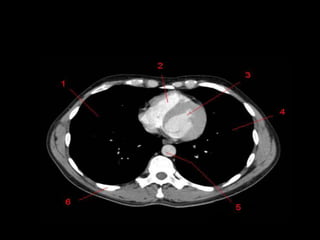

Mediastino Médio

• Pericárdio e seu conteúdo, arco aórtico e as

grandes artérias proximais, as artérias e veias

pulmonares centrais, traquéia, brônquios

principais e linfonodos.

• Nervo frênico e vago não são visíveis a TC.

• Janela Aortopulmonar

– Tecido adiposo, linfonodos, ligamento arterial e

nervo laringeo recorrente.

Mediastino Médio • Pericárdioe seu conteúdo, arco aórtico e as grandes artérias proximais, as artérias e veias pulmonares centrais, traquéia, brônquios principais e linfonodos. • Nervo frênico e vago não são visíveis a TC. • Janela Aortopulmonar – Tecido adiposo, linfonodos, ligamento arterial e nervo laringeo recorrente.